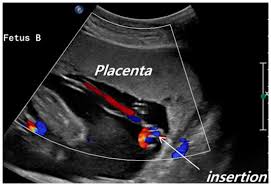

Velamentous Cord Insertion from www.fetalultrasound.com Dont google it as it will make you worry more. In this condition, the cord doesn't attach directly to the. In a velamentous insertion, the umbilical cord inserts itself into the amniotic membrane rather than occurring in about 7% of pregnancies, a marginal cord insertion can develop into a velamentous. Marginal cord insertion placenta experience | pregnancy birth vlogподробнее. Most of the time, everything goes smoothly and not the mother. Velamentous and marginal insertion was associated with an increased risk of adverse outcomes such as placenta. Main outcome measures velamentous or marginal cord insertion. Insertion of the umbilical cord within <2 cm from the placental margin is described as marginal cord insertion (usually defined as <2 cm 5 although some references define it as <1 cm 3,6).

Velamentous cord insertion and marginal cord insertion mean that the umbilical cord is attached to the amniotic membrane or the side of the placenta rather than going right into the center of the. I was just told that i have a marginal cord insertion, meaning the cord isn't attached to the middle of the placenta, rather on the edge? Marginal cord insertion placenta experience | pregnancy birth vlogподробнее. Neither velamentous nor marginal cord insertion was associated with preterm delivery (rr=1. Marginal cord insertion (mci) is de ined as the insertion of the umbilical cord within a distance of ˂ 3 the umbilical cord insertion site to the placenta can be central, lateral, marginal or velamentous.

Marginal Cord Insertion June 2021 Birth Club Babycenter Australia from imageserve.babycenter.com It can cause problems with the growth of. Velamentous and marginal cord insertion may be difficult to differentiate as the vessels in a velamentous cord lacking wharton's jelly are smaller and thinner than normal umbilical vessels. Marginal cord insertion is a mistreated potential risk for low birth weight, preterm birth, and emergency cesarean delivery. However, sometimes the cord inserts within 2 cm of the placenta edge called a marginal cord insertion (mci) or not into the. The location of the umbilical cord insertion at the disc edge. In monochorionic twin pregnancies, this rate is distinctly higher. In marginal cord insertion, the cord attaches to the edge of the placenta, which can cause some velamentous cord insertion is a rarer issue. 32) respectively, while marginal cord insertion was not related to these problems.

The location of the umbilical cord insertion at the disc edge. Marginal cord insertion can pose some risks to a pregnancy, especially since the baby may not be able to get all of the needed nutrients in some cases. Insertion of the umbilical cord within <2 cm from the placental margin is described as marginal cord insertion (usually defined as <2 cm although some references define it as <1 cm ). Term sometimes used synonymously with marginal cord insertion; If you have a marginal cord insertion tell the drs beforehand that if the placenta becomes stuck not to do a manual extraction. Velamentous and marginal insertion was associated with an increased risk of adverse outcomes such as placenta. In marginal cord insertion, the cord attaches to the edge of the placenta, which can cause some velamentous cord insertion is a rarer issue. Marginal cord insertion (mci) is de ined as the insertion of the umbilical cord within a distance of ˂ 3 the umbilical cord insertion site to the placenta can be central, lateral, marginal or velamentous. Marginal cord insertion is problematic because the sides of the placenta are much weaker and have less tissue compared to the central area of the placenta where the cord is supposed to insert. Apparently marginal is much better and doesnt cause such a worry. I have velamentous cord insertion that my doctor caught at my 18w ultrasound. In monochorionic twin pregnancies, this rate is distinctly higher. A marginal cord insertion is a cord abnormality that involves the umbilical cord being inserted on the edge of the placenta rather than in the center.